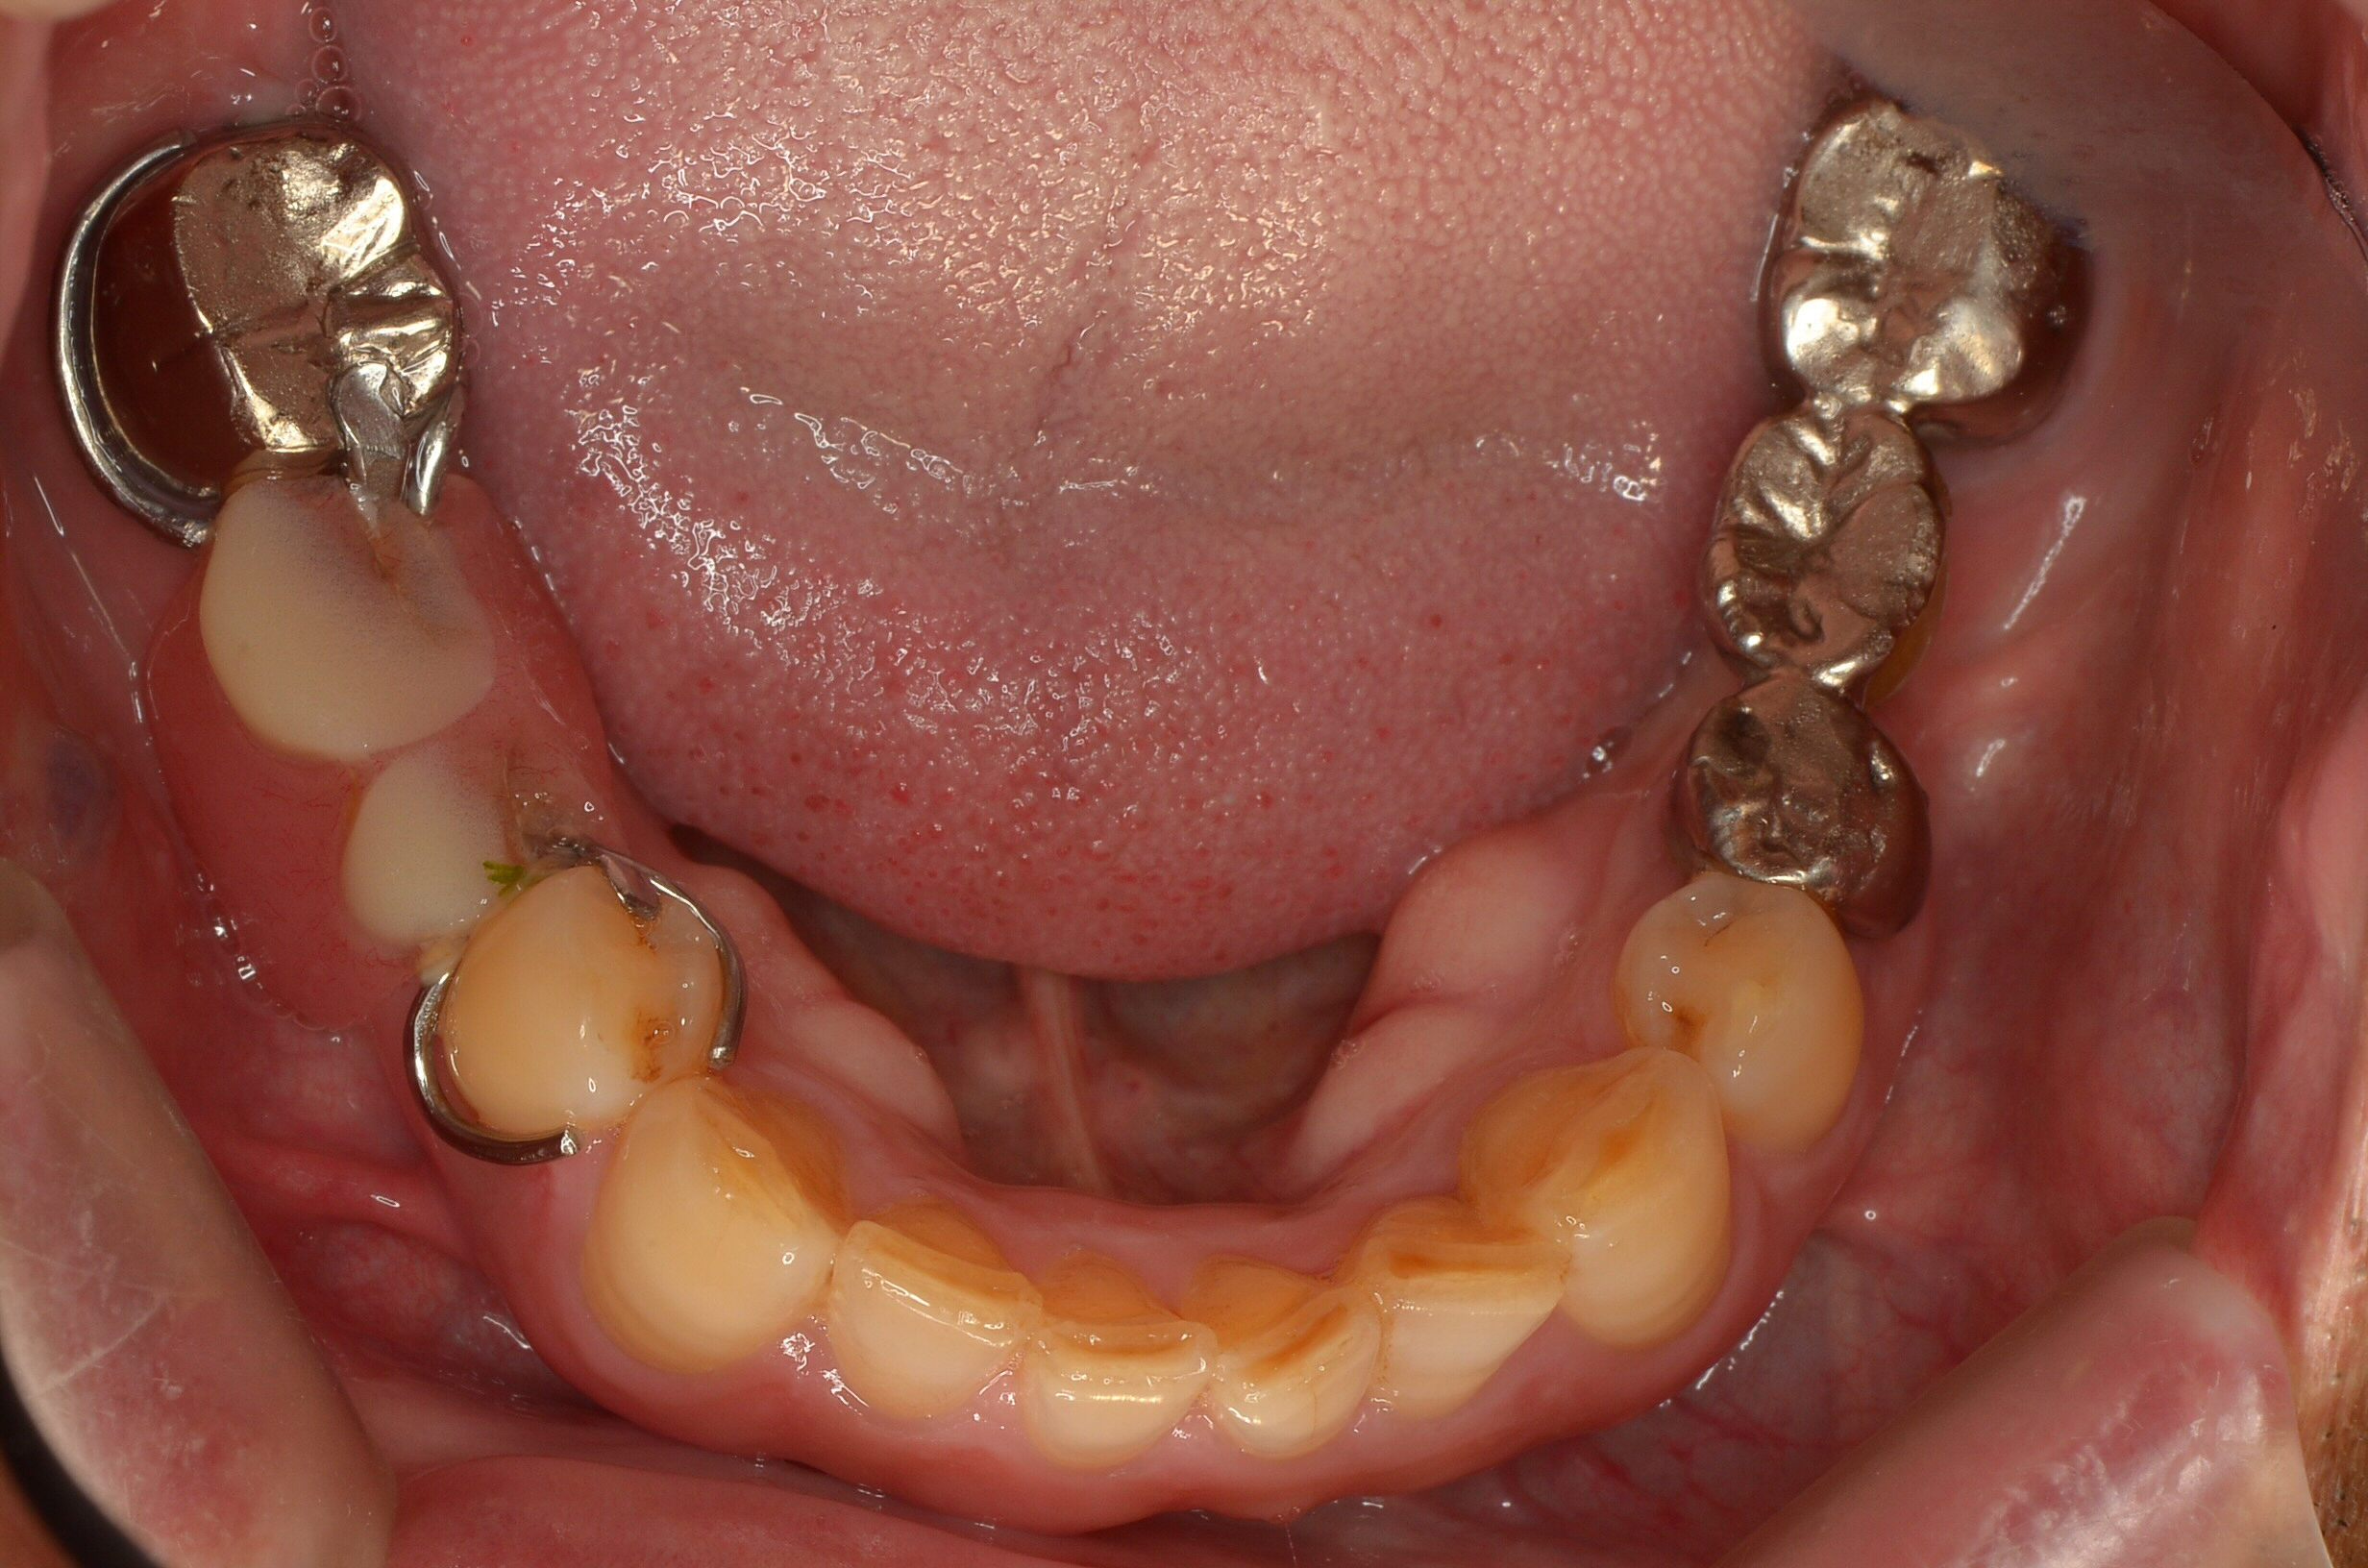

オープンバイト(開咬)のマウスピース矯正治療

Before

After

年齢

52歳

主訴

前歯でものが噛みきる事が出来ない。

治療期間

約2年

治療費

マウスピース型矯正装置 税込990,000円

治療内容

前歯でものを噛みきることが出来ず、年を取るにつれ奥歯が悪くなってきた気がするとのことでした。

ご相談させていただき、歯を抜かずにマウスピース矯正にて矯正治療を行わせていただきました。

治療期間は2年かかりましたが、見た目だけでなく前歯でしっかりものを噛めるようになり大変満足して頂けました。